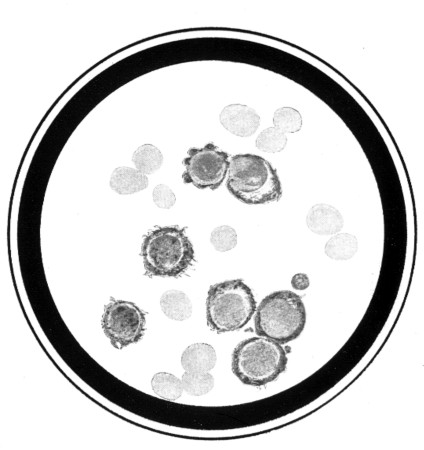

Fig. 1.

Fig. 1.Fraying out of the protoplasmic border in large lymphocytes. Free plasma elements formed by budding. ("Plasmolysis.")

(From a photograph of a preparation from chronic lymphatic leukæmia.)

To face page 72